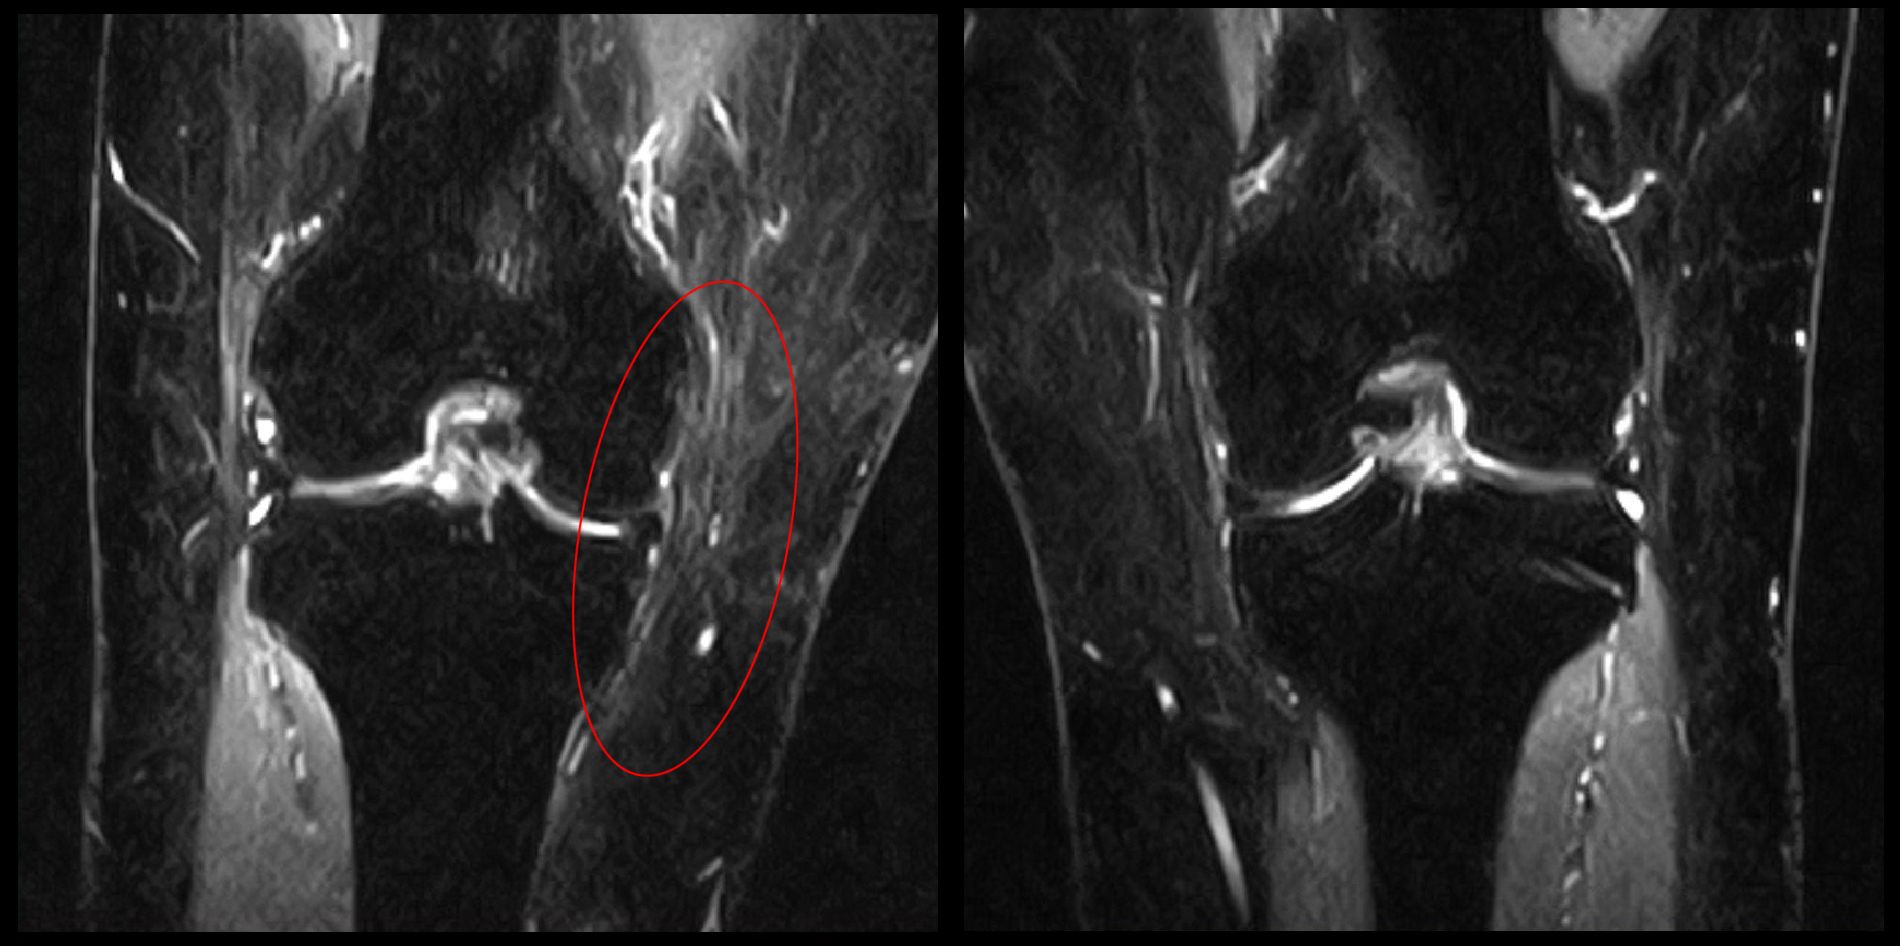

L3神経根ブロック像

すると、1週後には「けっこう痛い」というレベルの右膝痛は、「わずかに痛い」となり、患者さんはとても満足されることになりました。